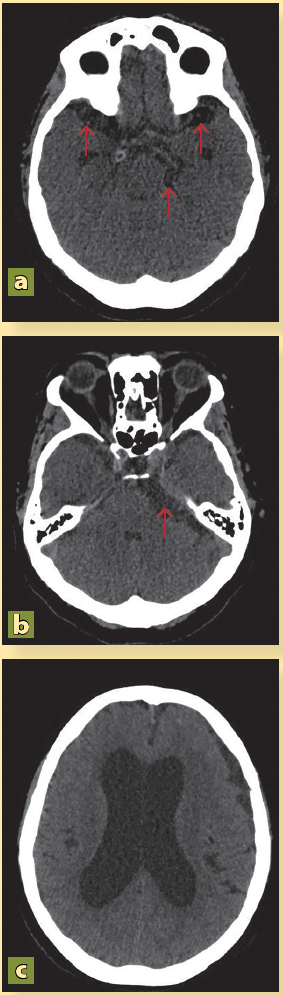

Se integra el diagnóstico de síndrome cefalálgico en relación probable con aumento de la presión intracraneal y crisis convulsivas, por lo que se justifica la realización de una tomografía axial computada (TAC) en donde se observa hidrocefalia, borramiento de surcos de la convexidad y la presencia de varias estructuras vesiculares en el espacio subaracnoideo de la convexidad, del giro temporal superior, así como en la cisterna prepontina y el ángulo pontocerebeloso, sugerentes de NCC activa (figura 1).

Se observa la presencia de quistes a nivel del giro temporal superior (a, flechas rojas), de la cisterna pontocerebelosa (b, flecha roja) y dilatación de los ventrículos (c).

Figura 1 Tomografía computada de paciente con neurocisticercosis al ingresar al servicio de urgencias